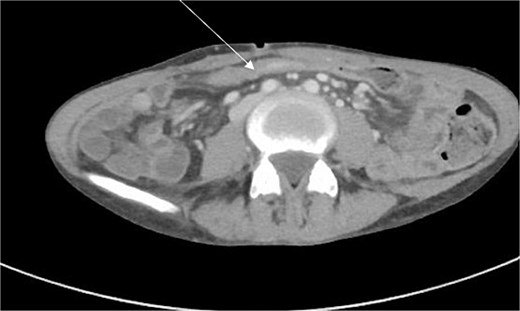

CT enterography demonstrated strictures involving the third and fourth portions of the duodenum with proximal gastric dilatation (Fig. 1), inflammatory changes in the transverse colon mesentery, and thickening of the neoterminal ileum (Fig. 2). Push enteroscopy confirmed a non-traversable stricture with multiple ulcers in the third portion of the duodenum; biopsies indicated chronic duodenitis. Colonoscopy revealed a non-traversable stricture at the ileocolic anastomosis, with biopsies showing severely active chronic enteritis (Fig. 3).

CT scan demonstrating thickening and abnormal enhancement of the neoterminal ileum (arrow), consistent with active CD.